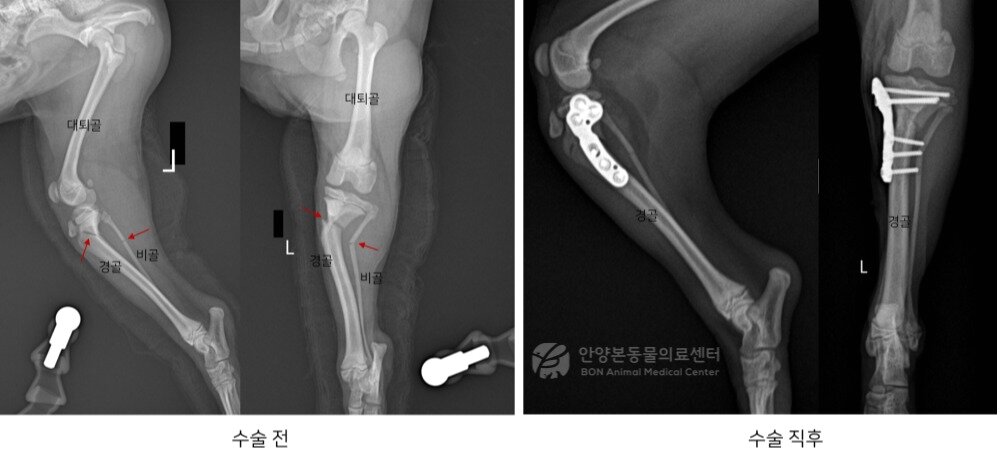

본문 이미지 - 수술 전후 방사선 사진(본동물의료센터 제공) ⓒ 뉴스1

수술 전후 방사선 사진(본동물의료센터 제공) ⓒ 뉴스1